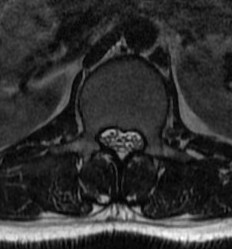

Spinal canal stenosis

- decreased inter-pedicular distance

- narrows from L1 down (normally increases)

- short pedicles